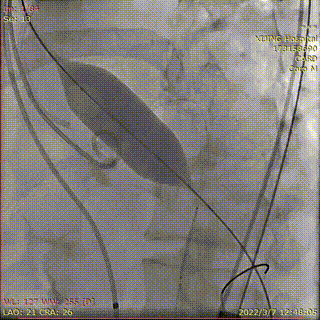

送入26mmVenus-A Plus造影定位

释放1/3瓣膜造影检查位置

释放2/3瓣膜

造影检查位置